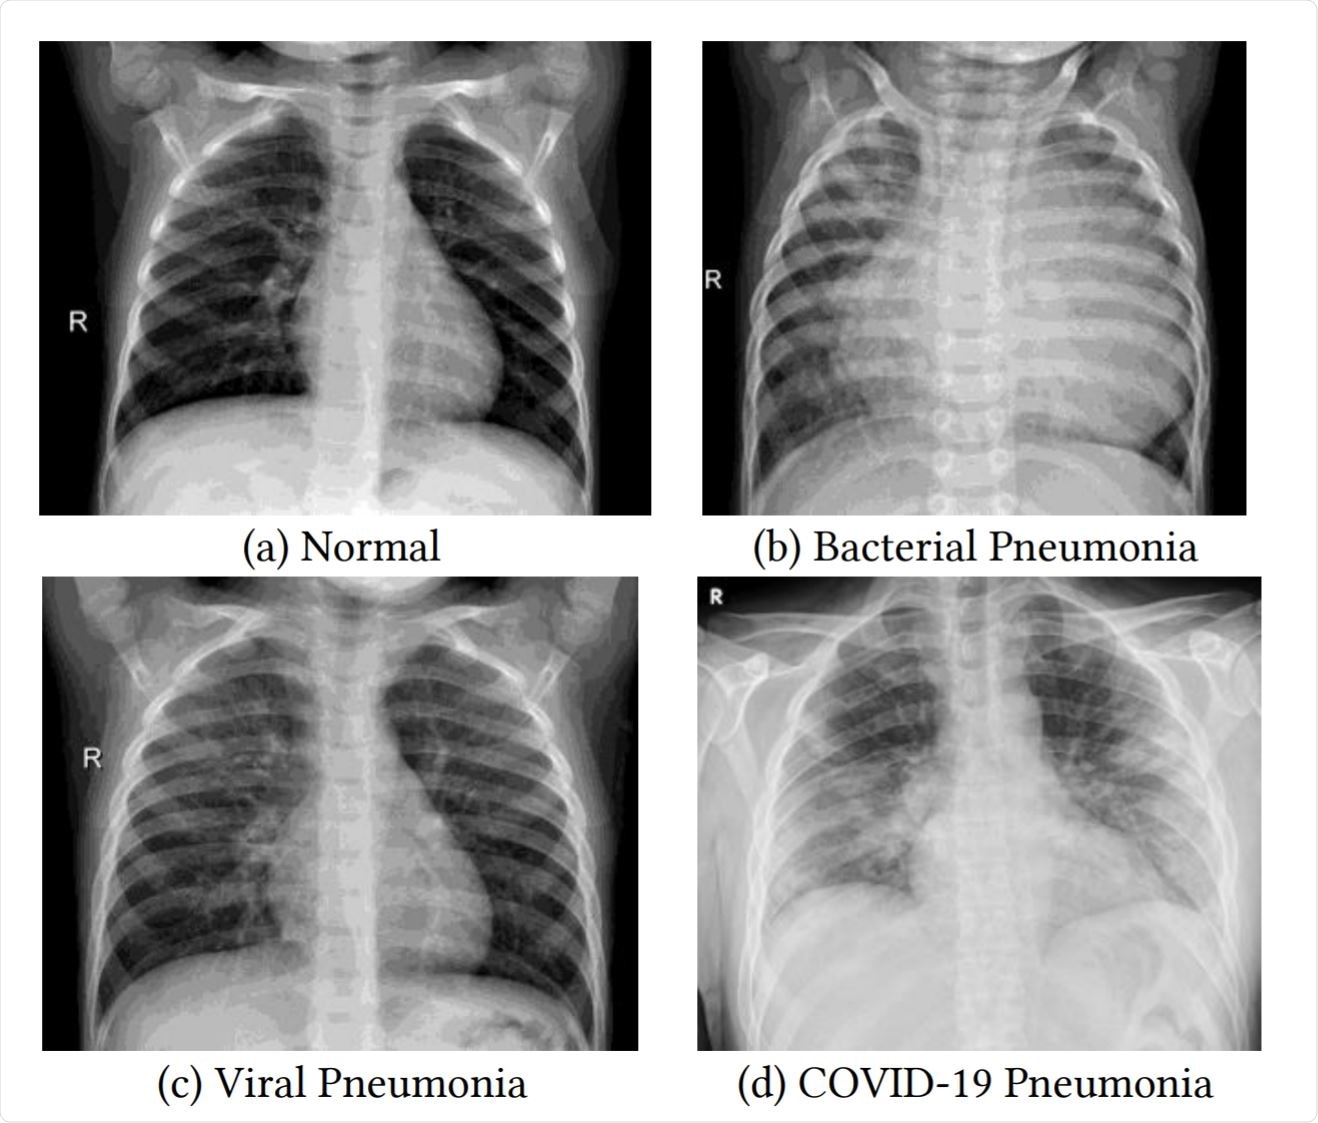

Zapalenie płuc na RTG klatki piersiowej objawia się zacienieniami, konsolidacjami i naciekami w miąższu płuc. Typowe są homogenne zmiany lobarne, przede wszystkim w dolnych płatach. Wczesne stadium może być subtelne lub niewidoczne. RTG umożliwia szybką diagnozę, ocenę rozległości i monitorowanie leczenia.

Zapalenie płuc na zdjęciu RTG objawia się przede wszystkim zacienieniami miąższu płucnego, które radiolog ocenia pod kątem rozległości i charakteru. W typowym obrazie bakteryjnego zapalenia płuc, takiego jak pneumokokowe, dominuje konsolidacja – homogeniczne zacienienie obejmujące cały płat płucny, np. dolny prawy (u 40-50% pacjentów wg badań z lat 2018-2022 w European Respiratory Journal). Nacieki zapalne tworzą „pianę” lub mleczne obszary, kontrastujące z przeziernością zdrowego miąższu. Wczesne stadia mogą przypominać mgłę (zacienienia szkliste, ground-glass opacities), szczególnie w wirusowych formach, jak COVID-19, gdzie wykrywalność sięga 60-80% na standardowym RTG klatki piersiowej. Radiolog szuka też poszerzenia naczyniowego lub linii Kerleya, wskazujących na obrzęk śródmiąższowy. Czy zawsze zapalenie płuc daje wyraźne zmiany na zdjęciu RTG? Nie – u 10-20% chorych obraz bywa subtelny, przede wszystkim w odmieńcach u dzieci lub starszych.

- Homogenna konsolidacja płata: klasyka pneumonii bakteryjnej, np. Streptococcus pneumoniae.

- Zacienienia szkliste (GGO): wirusowe etiologie, jak RSV lub SARS-CoV-2 (widoczne u 75% hospitalizowanych).

Jak odróżnić bakteryjne od wirusowego zapalenia płuc na RTG?

Bakteryjne zmiany są najczęściej jednostronne i ostre, z wyraźnym air bronchogramem – widocznymi oskrzelami wypełnionymi powietrzem na tle zacienionego miąższu. Wirusowe zapalenie płuc, np. wywołane grypą lub RSV, prezentuje się inaczej: dominują międzypłatowe nacieki o charakterze międzywrzodowym, rozproszone obustronnie. Te ziarniste lub siateczkowate zmiany zajmują oba płuca w 60-90% przypadków, bez homogennej konsolidacji.

Wirusowe postacie zapalenia płuc na zdjęciach rentgenowskich klatki piersiowej często przypominają obrzęk płucny, z perihilarnymi smugami i zagęszczeniami w dolnych polach. Bakteryjne zapalenie płuc wykazuje z kolei szybką ewolucję – konsolidacja może ustąpić po 48-72 godzinach antybiotykoterapii, co potwierdza RTG kontrolne. Frazy takie jak charakterystyczne cechy bakteryjnego zapalenia płuc w rentgenie pomagają radiologom w szybkim różnicowaniu.

Obraz radiologiczny wirusowego zapalenia płuc bywa subtelny, z hiperaeracją płuc i brakiem płynu w jamie opłucnowej, co odróżnia je od bakteryjnych ropni. W badaniach z lat 2010-2020, np. te publikowane w Radiology, aż 75% wirusowych przypadków wymagało potwierdzenia tomografią komputerową z powodu niejednoznaczności RTG. Te różnice między bakteryjnym a wirusowym zapaleniem płuc w obrazie rentgenowskim wpływają na dobór terapii.